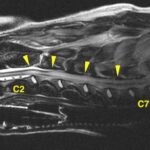

<症例情報> 小型ミックス犬7歳 避妊済みの女の子主訴:突然、左後ろ足に力が入りにくくなったことで来院神経の検査を行い、左後ろ足の反応の低下が認められた。背中か…